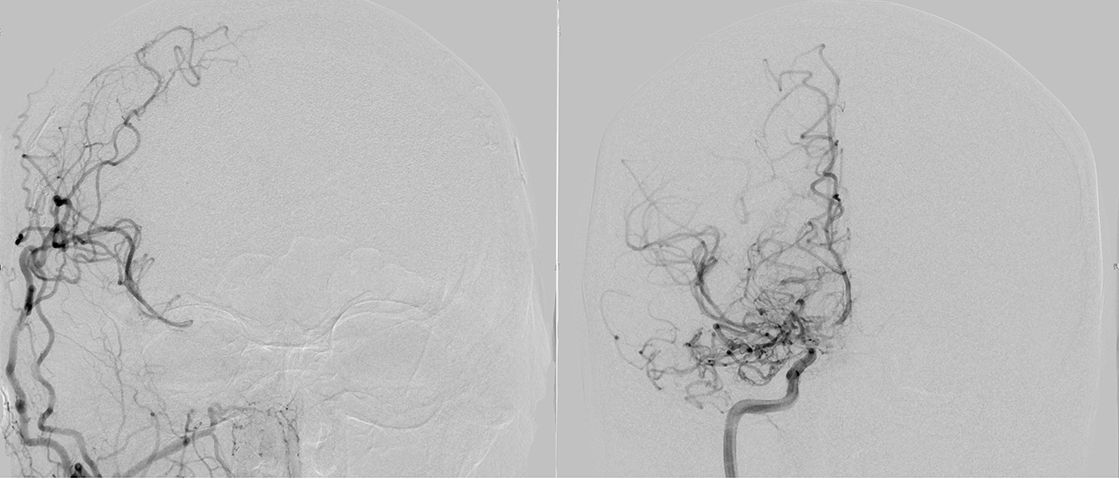

Die konventionelle cerebrale Angiographie ist die wichtigste Untersuchung zur Diagnosestellung der Moyamoya Krankheit. Diese Untersuchung ist zu vergleichen mit einer Herzkatheteruntersuchung, eben nur mit Darstellung der Hirnarterien. Bei Moyamoya-Patientinnen und Patienten werden, im Gegensatz zu Routineuntersuchungen bei anderen cerebralen Erkrankungen, selektiv die vordere und hintere Zirkulation des Gehirns dargestellt, sowie auch die Versorgung der extrakranialen Gefäße. Diese umfassende Darstellung ist besonders wichtig, um die vollständige Ausdehnung der Erkrankung zu erfassen und alle möglicherweise veränderten Blutflüsse im Gehirn zu verstehen. Je nach Befund werden die Engstellen der Hirnarterien, sowie auch mögliche begleitende Veränderungen selektiv hochauflösend dreidimensional dargestellt. Es ist wichtig zu erwähnen, dass die Moyamoya Krankheit nicht über eine Katheterintervention (Ballonaufweitung der Engstelle) behandelt werden kann und darf. Dies haben mehrere Studien gezeigt.

Angiographie beidseitige Moyamoya Krankheit

Konventionelle Angiographie eines Patienten mit beidseitiger Moyamoya Krankheit (links). 3-dimensionale Darstellung eines Aneurysmas einer jahrelang stark beanspruchten Spontan-Kollaterale (rechts).